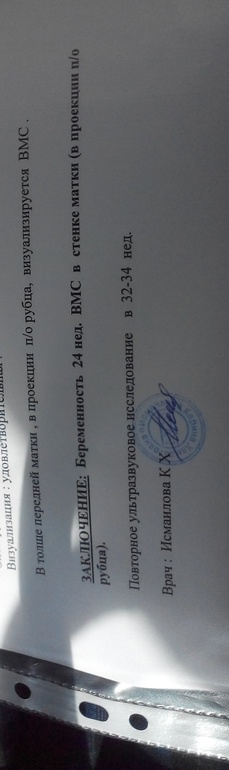

Ставила спираль нова-т два года назад ( через шесть месяцев после экс). Поставили,первый вечер были боли,потом все успокоилось. Через 10 дней пошла проверить как стоит вмс. При осмотре в кресле ее не нашли, сделала два разных узи и супер пупер узисток нашего города. Заключение-нет вмс . Меня убедили ,что я ее спустила в унитаз. Через месяц поставила вмс у другого врача,носила ее почти два года. Извлекли -в том же цикле забеременела. Делала узи в 7,13,16,20 недель (вмс никто не видел -три разных узистки). Сегодня пошла на узи и обнаружилось это е-мое !!!! Я в шоке. Сначала она решила что это миома,потом повертела и показала четкое изображение спирали !!!!! Спираль живет в стенке матки,в районе рубца ! Там где она давила датчиком ,именно в этом месте я ощущала покалывния несколько дней ,будто легкий удар током. Собственно из-за этого и пошла на узи то. Плацента по передней стенке . Спираль ей не мешает (пока). Она будто в какой-то капсуле круглой (на снимке).

Узистка сказала - пристально наблюдать за ее поведением,показать узи своему гинекологу . Гинеколог мой я уверена мне ничем не поможет,ибо ей просто плевать .... Куда бежать ? Что делать ? Жить буду ? Кому -нибудь знаком аналогичный идиотский случай ?😭😭😭😭😭.

Карина на дербентской . После этого ещё у буцаевой сделали ,типа не верю аьл в жк. Та говорит что не в рубце спираль ,а прошла насквозь матку и снаружи к ней прилегает